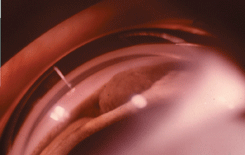

Опухоль растет медленно. Длительное время единственным симптомом изолированной меланомы цилиарного тела является относительная ;гипотония ;пораженного глаза. По мере роста опухоли соответственно локализации меланомы появляются резко расширенные эпибульбарные сосуды. При медикаментозном расширении зрачка в его просвете виден узел опухоли с гладкой поверхностью (см. рис. 22 на цветной вклейке). Передняя камера становится неравномерной: в зоне расположения опухоли радужка выступает кпереди, постепенно закрывает угол передней камеры, вследствие чего развивается вторичная глаукома. При распространении пигментированной меланомы на угол передней камеры появляется симптом “ложного иридодиализа”. Если опухоль прорастает дилятатор радужки, зрачок приобретает неправильную форму (симптом “уплощения зрачка”). Вследствие дислокации хрусталика и развития ;контактной катаракты ;снижается острота зрения.

Рисунок 22. Иридоцилиарная меланома. Гониоскопическая картина: в углу передней камеры виден пигментированный узел опухоли